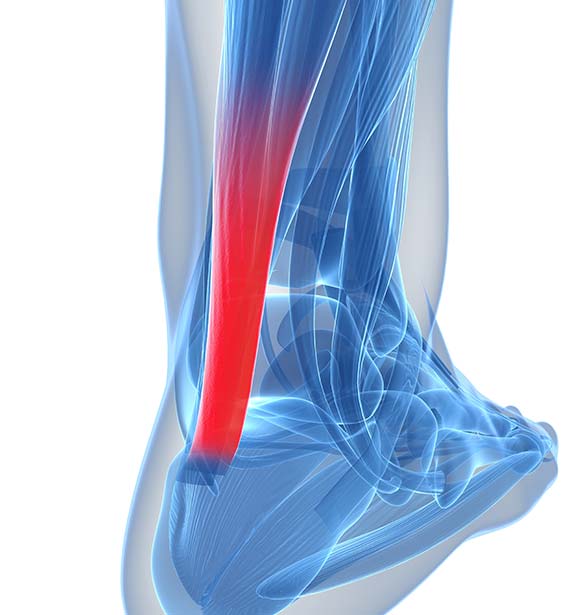

pictures of achilles tendon

ACHILLES TENDINOPATHY – Step Relief Podiatry

Achilles Tendinitis: Causes, Picture, Symptoms And Treatment

Achilles Tendonitis Causes, Symptoms & Treatment